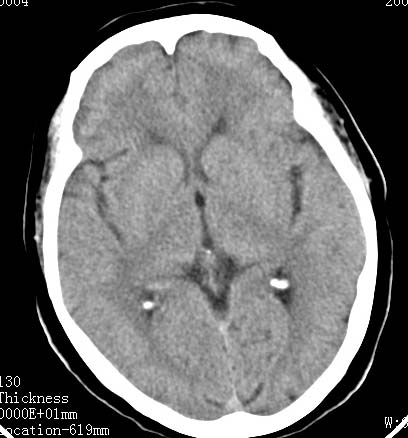

标题: CT17832:女性病人 65岁语言障碍一天 [打印本页]

女性病人 65岁语言障碍一天

左脑额顶等底密度肿块,灶周水肿明显,占位效应(+),考虑为转移瘤.(不考虑是胶质瘤.)

病灶中心为等密度,周边绕以低密度水肿区,考虑左额叶占位性病变。